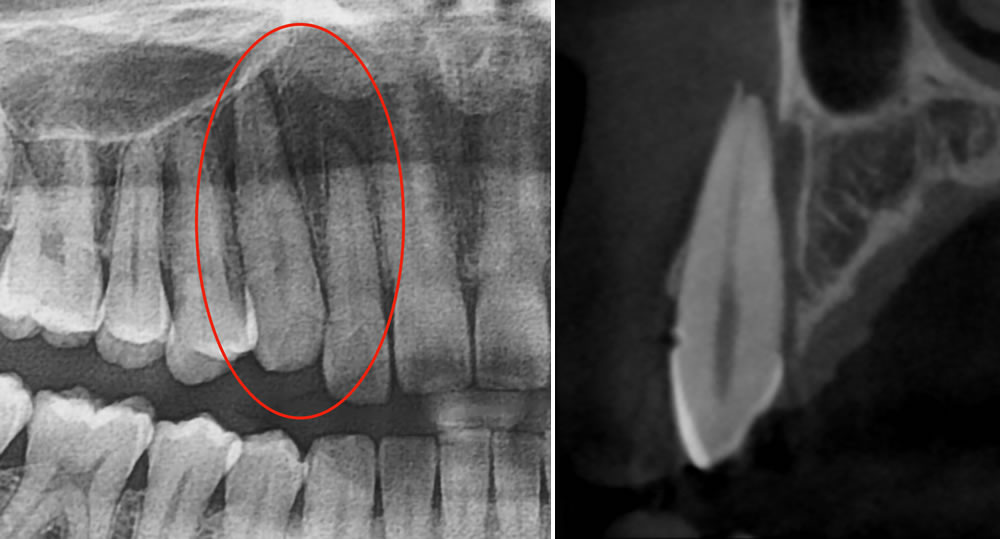

こちらの患者さまは、夜間に転倒して歯がずれたとのことで初診来院されました。青丸で囲まれている2本がずれていることが確認できます。

初診時のレントゲン画像・CT画像

初診時のレントゲン写真とCT画像です。犬歯に至っては、大きく外に飛び出ていることが確認できます。